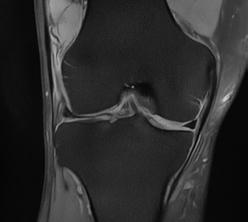

PD STIR - 1024 x 1024 matrix - 3mm slice thickness

Sag T2 - 0.5 x 0.5 min - 0:56 min Ax PD FatSat - 0.6 x 0.6 mm - 1:30 min Cor PD FatSat - 0.6 x 0.6 mm - 1:15 min Cor PD - 0.5 x 0.5 mm - 0:58 min © 2020 CANON MEDICAL SYSTEMS // MREU200040

Fast knee protocol with AiCE on Vantage Orian 1.5T